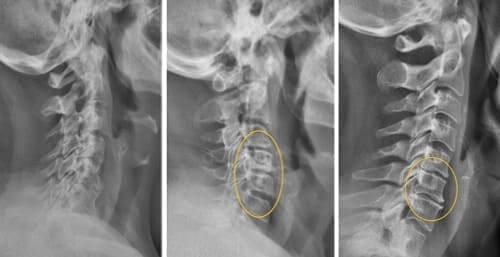

— Apakah Anda benar-benar berpikir bahwa pijat atau analgesik dapat mencegah kerusakan sendi dan tulang rawan? Itu adalah kesalahpahaman besar. Obat-obatan dari apotek tidak dapat meregenerasi jaringan, sementara bahan kimia yang terkandung di dalamnya justru merusak hati dan ginjal seiring waktu. Tubuh tidak dapat selamanya menanggung beban racun ini, dan alih-alih menyelesaikan masalah, Anda justru meracuni diri sendiri! Hal ini terutama berlaku untuk tulang belakang. Semua sendi mengalami keausan, tetapi pada tulang belakang, kurangnya ujung saraf dapat menyembunyikan perubahan yang berbahaya. Kompresi saraf skiatik akibat hernia adalah proses yang menyakitkan, awalnya menyebabkan nyeri ringan di punggung bawah, lalu menjalar ke kaki, menyebabkan kesemutan, mati rasa, dan akhirnya hilangnya fungsi kaki sepenuhnya. Kerusakan yang terus berkembang akan menyebabkan kelumpuhan pada bagian bawah tubuh, dan mengembalikan kendali atasnya menjadi hampir tidak mungkin. Lihat gambar ini. Ini adalah kondisi tulang belakang seseorang yang baru berusia 44 tahun, tetapi tampak seperti lansia. Dulu, kerusakan seperti ini hanya terjadi setelah usia 60 tahun, tetapi sekarang hal ini menjadi umum bagi mereka yang baru saja melewati usia 40 tahun. Kerusakan ini akan terus berkembang seiring bertambahnya usia, dan mengabaikannya berarti menempatkan diri dalam risiko kelumpuhan total!

Tulang belakang pasien berusia 44 tahun: semuanya dimulai dengan nyeri ringan, tetapi hanya dalam satu minggu muncul hernia, dan dalam dua minggu terjadi pergeseran tulang belakang, tekanan pada saraf, dan akhirnya—kursi roda.

Hernia cakram tulang belakang, kompresi saraf, kehilangan sensasi, dan kelumpuhan parsial pada kaki.